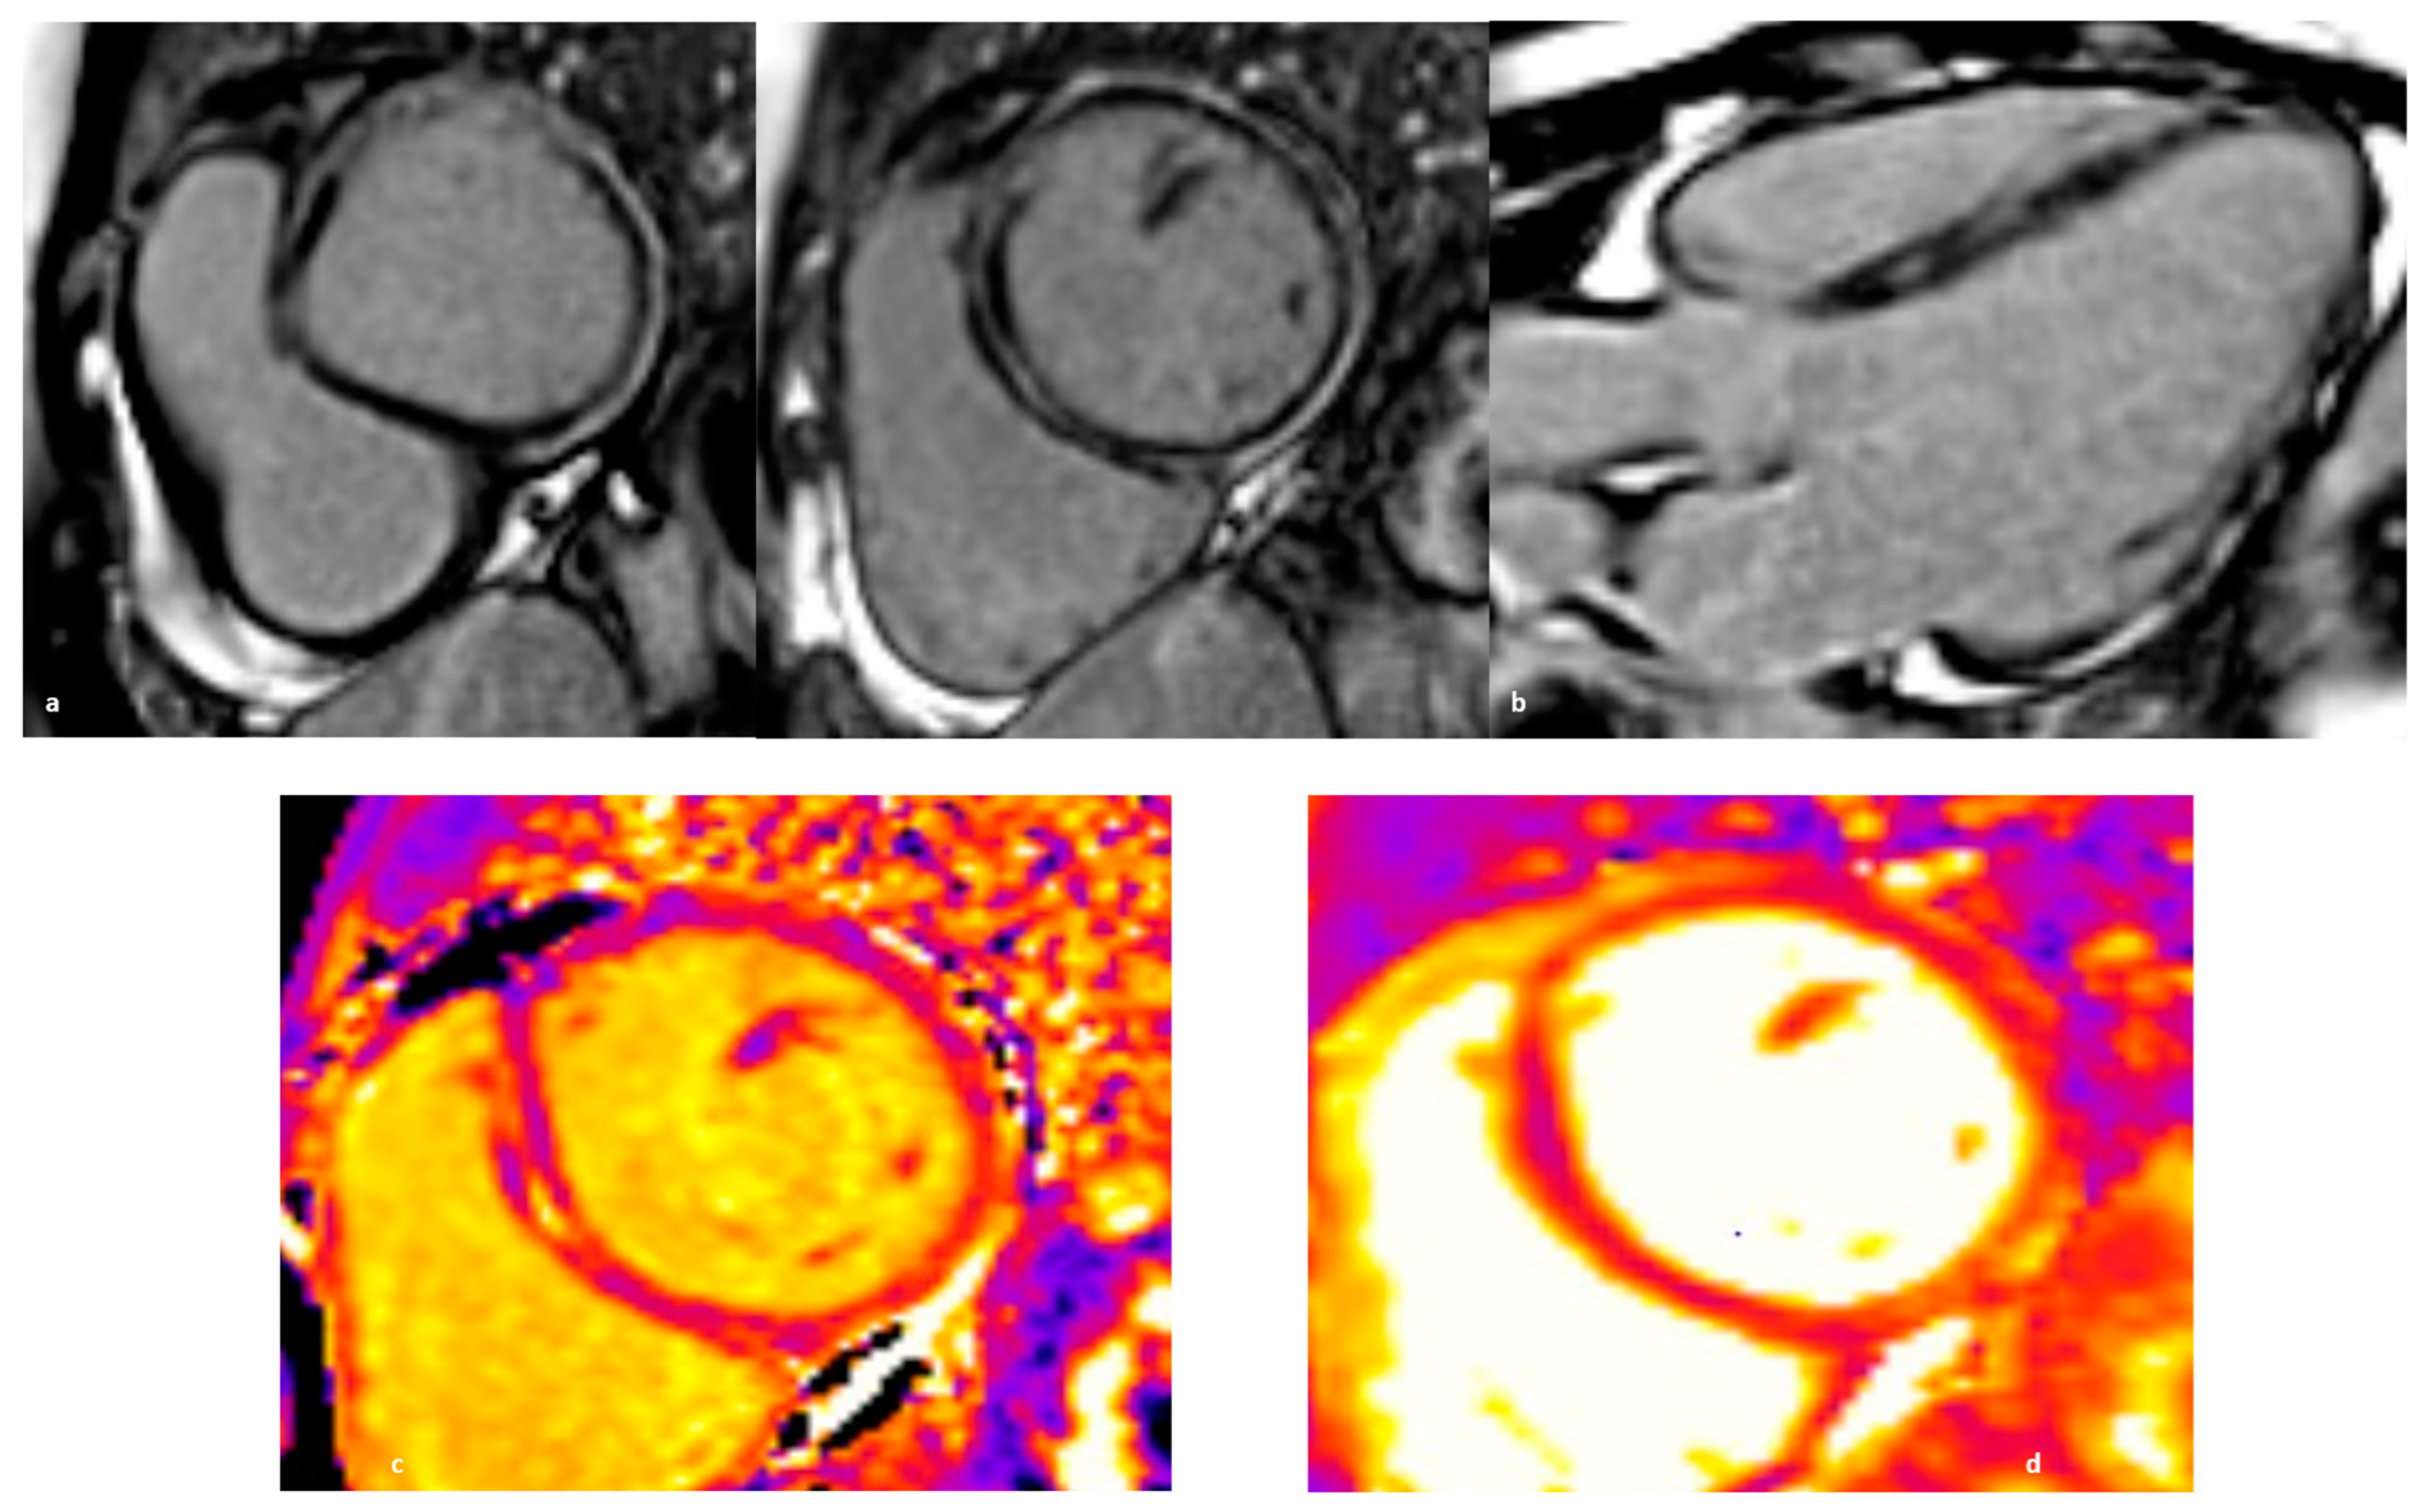

3.2. Clinical Features and Diagnosis

5.1. Pathophysiology

5.3. Diagnostics